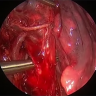

This video shows a left upper lobectomy with wedge resection of the pulmonary artery, sleeve bronchoplasty, and mediastinal lymph node dissection in a 36-year-old female patient.

Intraoperative events during VATS lobectomy should be expected. The management of these events is critical to achieving a good patient outcome. This video advocates for a preventative strategy, practicing event management, and communicating specific skills to address intraoperative events such as pulmonary artery bleeding.

This video presents a single-port VATS right upper lobe sleeve lobectomy for a stage I carcinoid tumor in a 52-year-old patient. Sleeve lobectomy is a challenging and complex procedure. Typical carcinoids occluding the right upper lobe bronchus present an ideal opportunity for sleeve upper lobectomy due to their indolent nature and excellent oncologic outcomes.